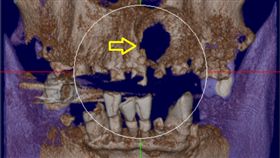

牙齒蛀爛長膿包不理會 顎骨破大洞!

牙齦長膿包,不要以為擠破就沒事。新北市一名中年大叔,...